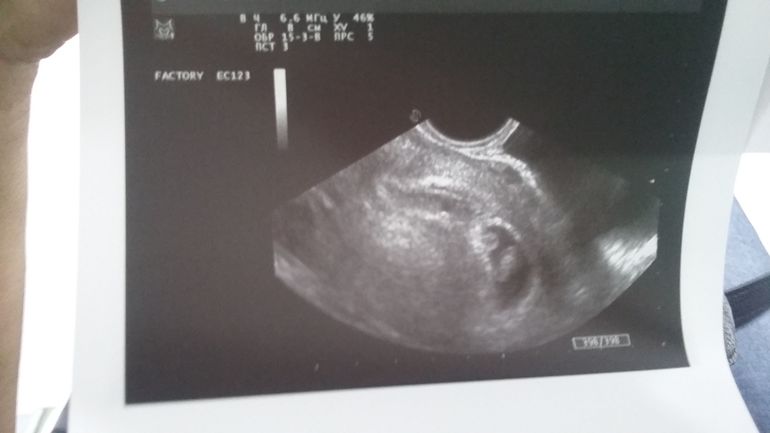

УЗИ. 7 недель. Шок.

Эмоции, странности, тревогиСъездила на Узи. Смотрит и тут говорит. Что-то вижу... Как буд то второй... Но нет плодного яйца. Я говорю кто второй? Она эмбрион. Говорит похоже.. Но утверждать пока не могу. Вышла я в недоумении. И бегом к врачу. Говорю так и так. И она сразу очень похоже на близнецов. Однояйцевых. Дала телефон грамотного узиста. Завтра еду к ней. Для подтверждения. Ох меня трясёт!))))Как до завтра дожить, я наверное спать не смогу) Не ожидала я такого!:))))

И правда похоже на двойню, это же круто, особенно однояйцевые, редкость большая, недавно думала как это здорово когда 2 одинаковые ляльки )